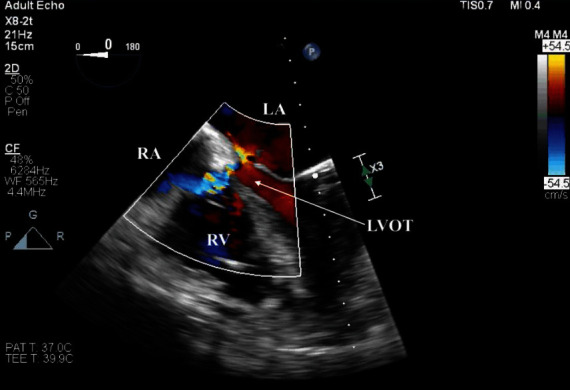

The Gerbode defect was first described in the late 1950s as a congenital peri-membranous ventricular septal defect (VSD), resulting in a left to right ventriculoatrial shunt. We present a case of a patient with restenosis of a prior bioprosthetic aortic valve (AV) who underwent reoperative AV replacement (AVR), which was complicated by a unique iatrogenic Gerbode defect with concurrent LV-LA communication. Our case highlights the unique complications resulting from ventriculoatrial shunts, with consideration paid to the management of ventriculoatrial defects described.